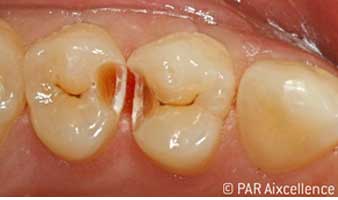

Рис. 5. На этапе экскавации четко виден кариозный процесс; апроксимальные фиссуры, как кажется, не содержат измененных тканей

Рис. 6. Изображение, как на рис 5, на этот раз с использованием Facelight. Теперь кариес четко распознается и в фиссурах